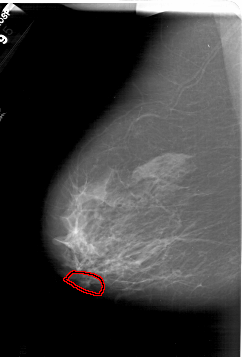

FILE: A_1386_1.LEFT_MLO.OVERLAY

TOTAL_ABNORMALITIES 1

ABNORMALITY 1

LESION_TYPE CALCIFICATION TYPE AMORPHOUS DISTRIBUTION LINEAR

ASSESSMENT 4

SUBTLETY 1

PATHOLOGY BENIGN

TOTAL_OUTLINES 1

BOUNDARY

LEFT_MLO LINES 6421 PIXELS_PER_LINE 4351 BITS_PER_PIXEL 12 RESOLUTION 43.5 OVERLAY